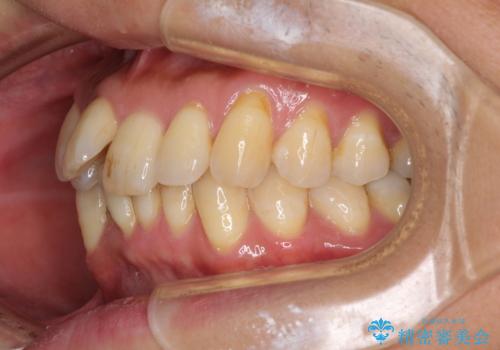

前歯のデコボコ ワイヤー装置での短期間治療

- 前歯のデコボコを気にして来院された患者様です。

インビザラインまたはワイヤー装置、どちらでも対応可能でしたが、自己管理の少なさ、期間の短さから、ワイヤー装置による矯正治療を行うこととしました。

治療開始の頃は、食事や歯磨きが慣れず、装置が頻繁に脱落しましたが、2,3ヶ月ほどで慣れ、その後は1年ほどで治療を終えることができました。